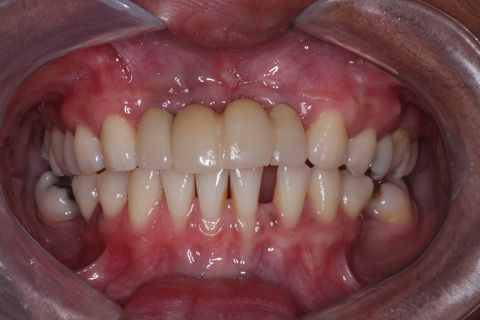

Provisórios instalados . Foto com um ano e meio após a instalação do enxerto e dos implantes. Paciente não compareceu antes para a finalização do trabalho devido problemas particulares

Minipilares instalados. Nota-se apenas 3 minipilares pois um dos implantes foi perdido. Instalamos um novo implante que também foi perdido. Optamos em manter apenas 3 implantes e finalizar a prótese fixa parafusada.

Paciente do sexo feminino, 32 anos e 10 mêses de idade, com ausência dos incisivos centrais e laterais superiores, associado a um defeito ósseo vestibular côncavo. Realizamos planejamento reverso, ou seja, enceramento diganóstico prévio para avaliação do defeito ósseo em termos de quantidade e do posicionamento final das próteses. A paciente foi submetido a um enxerto ósseo autógeno do ramo ascendente lado direito e fixação dos blocos ósseos na área receptora, com fixação dos mesmos através de parafusos de fixação com cabeça expandida Neodent. Após 6 meses foram instalados 4 implantes Neodent.

O caso clínico ainda está em andamento. A paciente atualmente está fazendo uso de próteses provisórias e está sendo feito controle gengival para posteriormente serem instaladas a prótese definitivas.